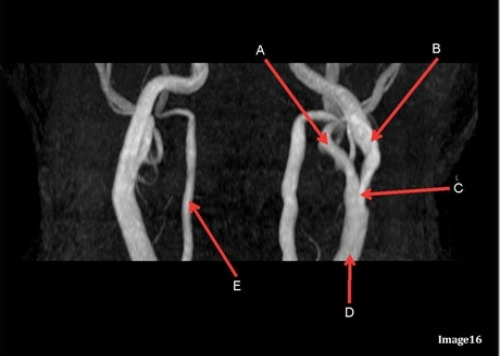

Image 9 is an example of a _____ weighted sequence acquired in the ______ scan plane.

C. T2; Axial

Letter E in Image 9 is pointing to:

C. Frontal Sinus

Letter C in Image 9 is pointing to:

A. Third ventricle

Letter A in Image 9 is pointing to:

D. Caudate nucleus

Letter D in Image 9 is pointing to:

C. Lentiform nucleus

Letter B in Image 9 is pointing to:

B. Thalamus